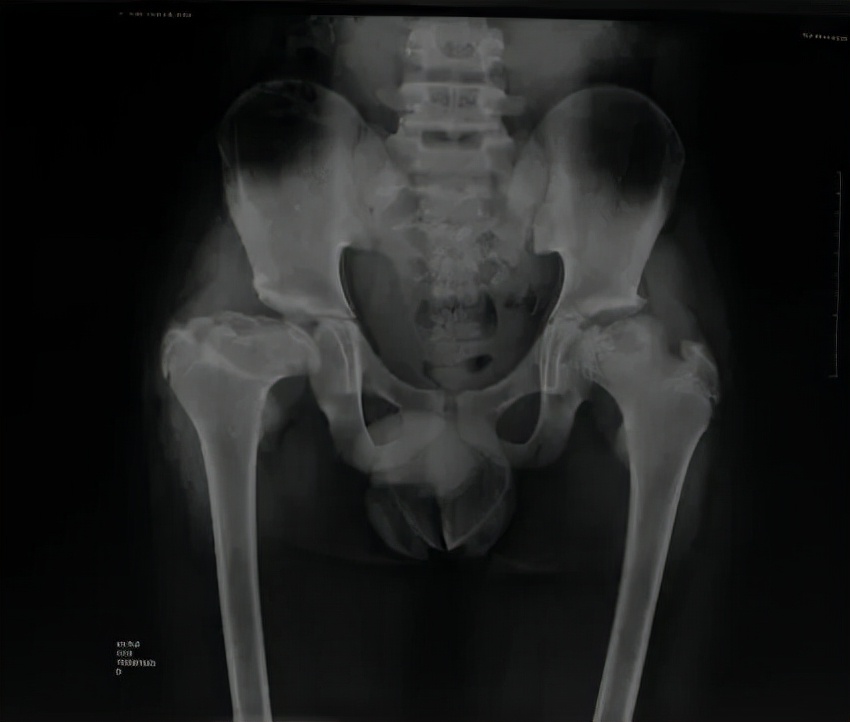

Perthes病即 儿童股骨头特发性缺血性骨软骨病,于1910年被Legg、Calve、和Perthes三位学者总结报道,因此也称为Legg-Calve-Perthes病,简称LCPD。发病早期,患儿往往出现跛行和患侧大腿中下段的疼痛不适、有时甚至是健侧膝盖周围疼痛,休息几天就可以缓解。但由于儿童天性活泼好动,上述症状常常容易复发。因此好多孩子常常被家长乃至初诊医生忽视、只是简单认为是“滑膜炎”、“缺钙”或者所谓“生长痛”,没有早期发现并且及时确诊、科学施治,而遗留了头臼曲率适应不佳、髋臼覆盖不良、股骨近端形态异常等等生长发育畸形(图1),导致髋关节出现软骨磨损继而早发骨性关节炎,从而严重影响日常生活和工作。而如果能够早发现早治疗,LCPD完全可以获得优良结果乃至正常髋关节状态(图2)!

图1 LCPD影像学表现,股骨头变形,髋关节覆盖差